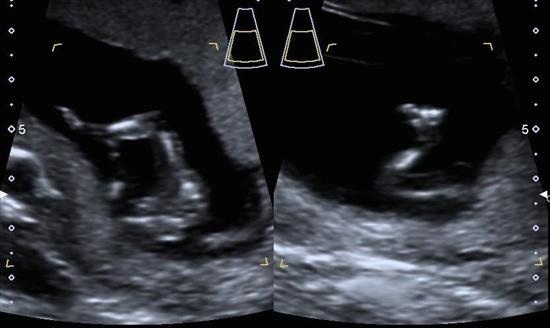

This was from my scan at 12+6, I've been driving myself crazy googling what 2 lines means so any guesses hugely appreciated!!

I think you've got a lil boy in there! :) Now I could be wrong...but with 3 boys, I have some confidence in this guess. (I believe those two lines you are referring to in the first picture are testicles) Surely others will chime in!

Looks like a little boy to me also! And if you look to the left of the two lines something is peaking out;) I definitely see a "turtle".

Thanks all! I'm convinced boy too, although a friend who did a stint as a u/s tech said it's still to early to tell and could go either way.....maybe she was just trying to instil pink hope, as it looks very blue to me!

Thanks so much everyone. I decided to go for a gender ultrasound today as I'm now 18 weeks. Shock of my life but baby is 100% GIRL!!!!!